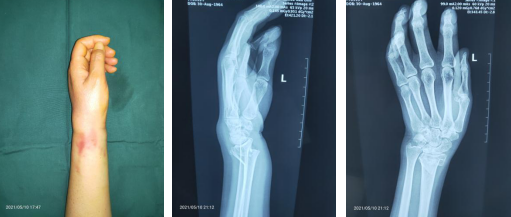

2021年5月,家住徐州的李阿姨在打网球时身体后仰摔倒,当时其左手着地致腕部肿胀、畸形,活动受限。李阿姨随即到附近的一家医院就诊,拍片显示:左桡骨远端骨折。医生予以手法复位石膏外固定,拍片显示骨折线对位欠佳,如是几次。李阿姨及家人考虑手法复位效果欠佳,于是来到betway在线登陆想寻求更好的治疗。当天,正好是手外二病区的齐伟亚主任坐诊,齐主任为李阿姨进行相关检查,诊断左桡骨远端骨折、左舟骨骨折。齐主任介绍,我院采用腕关节镜辅助下复位桡骨远端骨折,切口小,恢复快,李阿姨稍作考虑,便决定行微创手术治疗。

术前外观(左图)术前X线